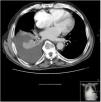

Se realizó una TC torácica en la que se observó derrame pleural derecho libre de 5cm de espesor, que provocaba atelectasia pasiva del lóbulo inferior derecho (fig. 1), sin otras alteraciones.